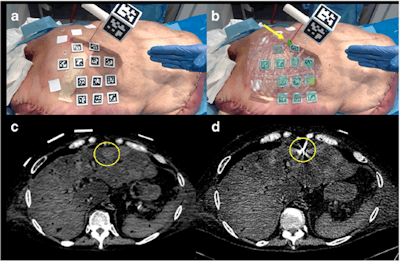

They created their augmented reality software (Endosight, R.A.W.) in a computer program (Unity 2017.1.1, Unity) and designed the software to superimpose 3D images directly onto a target. The augmented reality device includes a customized needle handle and a tablet (Microsoft Surface Pro 4, Microsoft) attached to a tripod that can display 3D images through its camera.

To test the accuracy of the technology, the researchers simulated needle insertion for thermal ablation using the augmented reality device on three different models: a custom-made silicone phantom, a pig, and a cadaver with liver metastases.

First, they placed radiopaque skin markers on each of the models, acquired and processed CT scans of the models, and converted the scans into 3D images for the augmented reality software. Then the investigators used the augmented reality device to project these 3D images directly onto the corresponding model. This allowed the clinicians to visualize the targeted area for insertion in relation to relevant internal structures as they maneuvered the needle.

Overall, the tests for augmented reality guided needle insertion demonstrated extremely high accuracy -- within the threshold of 5 mm from the targeted site. The average distance between the geometric center of the model and the augmented reality images was 2 mm for the phantom, 3.9 mm for the pig model, and 2.5 mm for the cadaver. The mean distance was 2.8 mm for the two liver tumors in the cadaver.